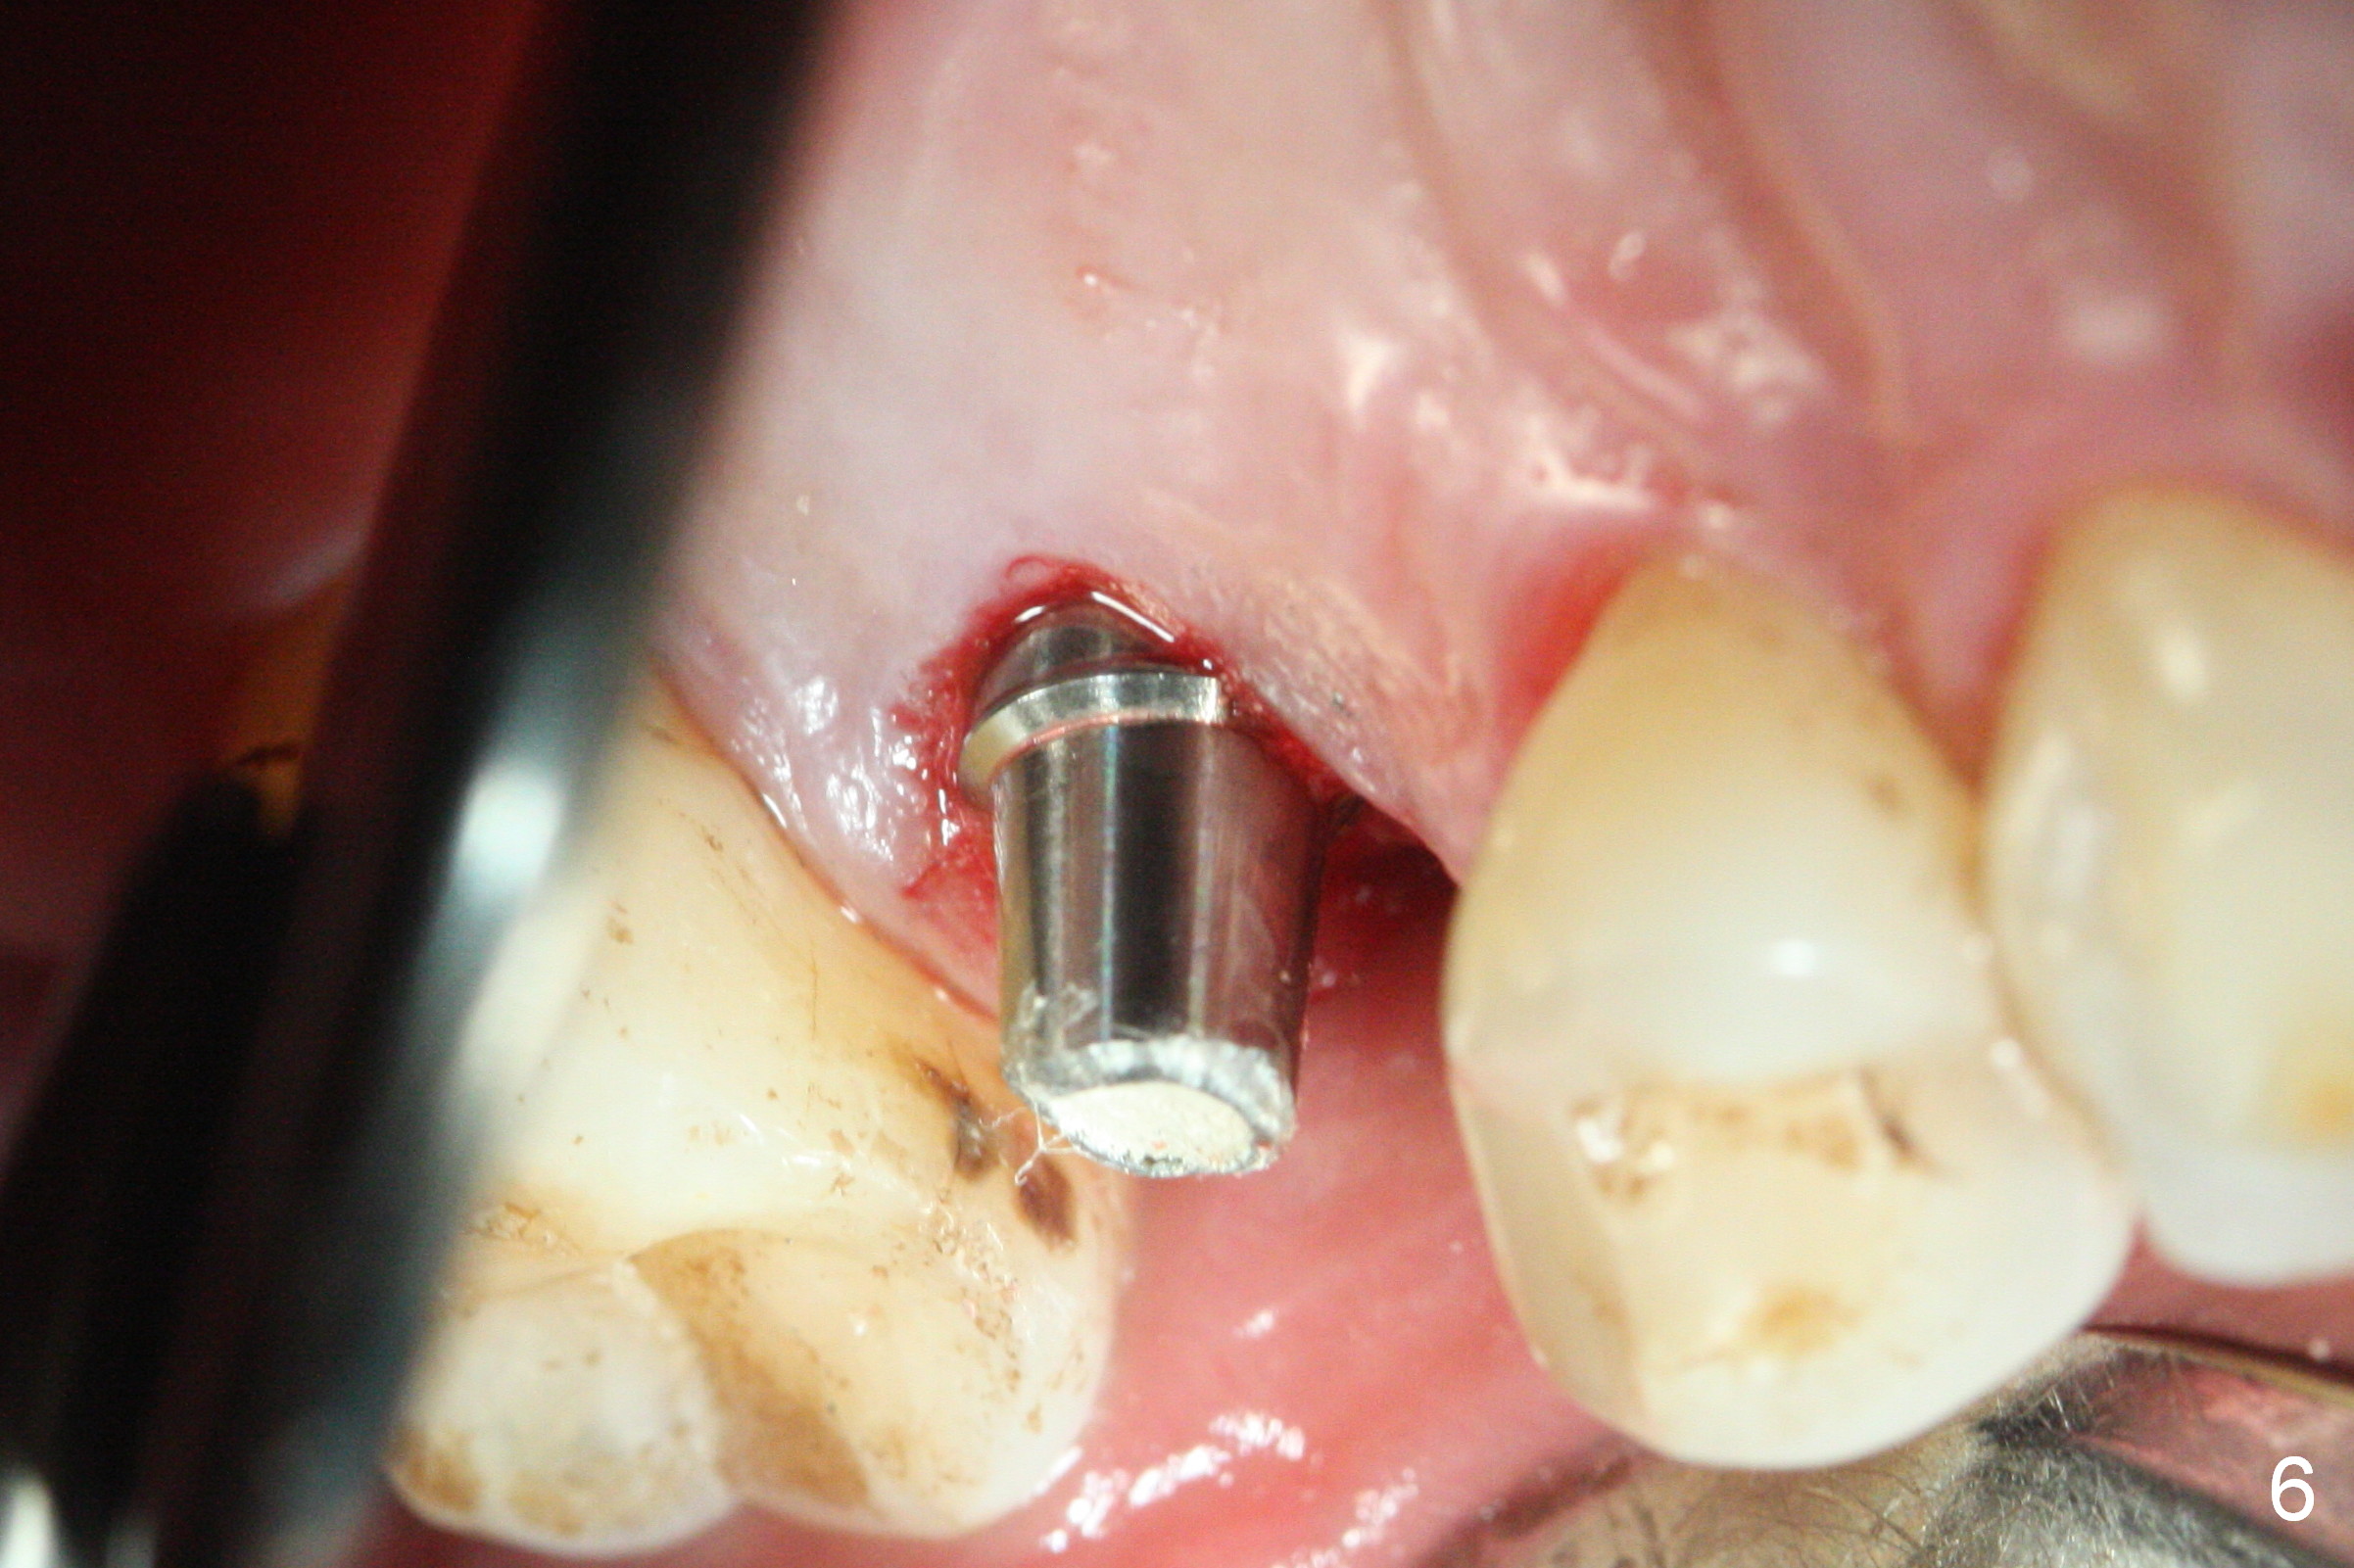

Initial osteotomy depth is 18 mm (Fig.1 green line) with 9 mm in the native bone (red line). The bone density feels to be low. There is at least 2 more mm bone apically (pink line). The depth is increased by 2 mm so that when a 3.8x15 mm implant is placed, there is 10-11 mm implant/bone contact (Fig.2 red line). There is large bony defect (Fig.3 *), which is bone grafted (Fig.4 *). Finally a longer abutment is placed (4.5x5.5(5) in Fig.4 vs. 4.5x4(5) in Fig.2,3). The 5 mm cuff does not look too long buccally (Fig.5) or palatally (Fig.6). To prevent postop buccal gingival overgrowth (2), the buccal margin of an immediate provisional is subgingival (Fig.7-9 *). Bone density between #13 and 14 appears to increase 3 months postop (Fig.10). The implant seems to be equi-crestal (Fig.11 ^). There seems to be more bone growth (i.e., decreasing gap) 6 months postop (Fig.12). Impression is taken. A crown is delivered nearly 7 months postop (08/07/2017). While there is minimal bone loss at #13 and 15 three years and 4 months post cementation, the tooth #14 and 18 are mobile (Fig.13,14).